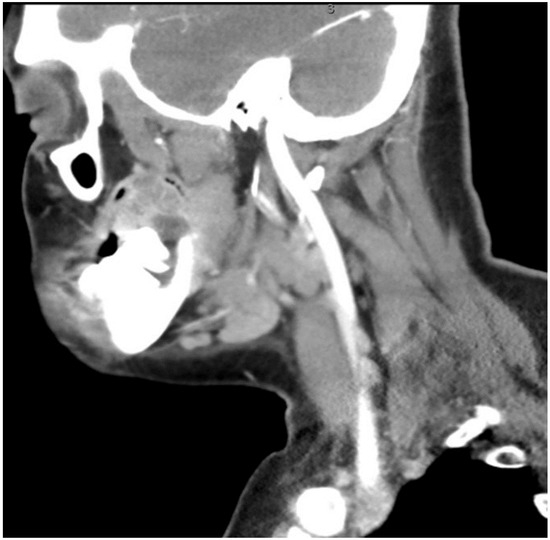

Figure 3.

CT neck with contrast showing the enlarged lymph node at level 1B.